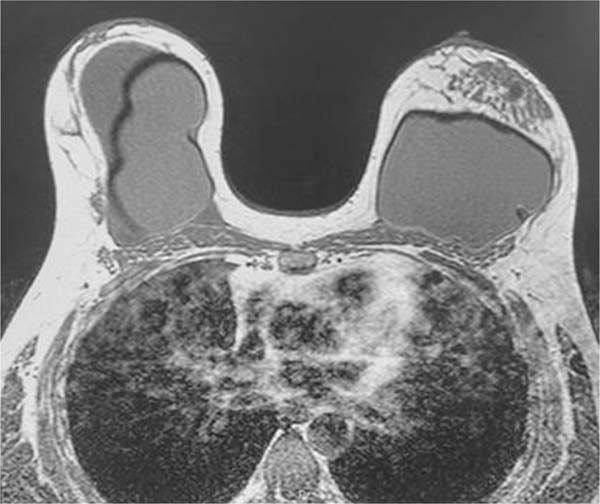

Magnetic resonance imaging showed an extensive intracapsular collection in the right breast with heterogeneous content, associated with enhancement and thickening of the fibrous envelope and capsule, consistent with an inflammatory process and capsular contracture. It was not possible to rule out BIA-ALCL. The Breast Imaging-Reporting and Data System (BIRADS) was 4 (►Fig. 2).

Fig. 2 - Breast magnetic resonance imaging of the patient from August 2021 showing single-lumen, retroglandular silicone implants with anterior closure inserts (potentially representing rotation) and no signs of intraor extracapsular rupture. Large, heterogeneous intracapsular collection on the right side, associated with enhancement of the fibrous capsule. Small amount of pericapsular fluid on the left side, associated with delayed capsular enhancement.